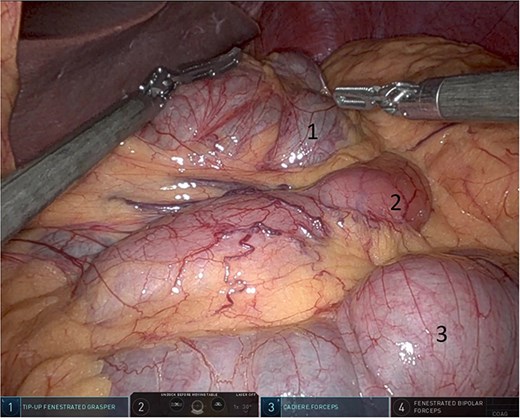

Upon entering the abdominal cavity, dilated bowel loops were observed (Fig. 2), and a significant portion of the colon was found herniated through the foramen of Winslow (Fig. 3). The herniated colon was covered by the pars flaccida (Fig. 4) (Video S1). Careful dissection was performed anterior to the hepatoduodenal ligament (Fig. 5). The gall bladder was retracted to the patient's right upper quadrant, which allowed for the retraction of the foramen of Winslow (Fig. 6) (Video S1). After carefully placing the tip of the instrument posterior to the portal vein and gently elevating it, the herniated colon was successfully reduced (Fig. 7) (Video S1).

Herniated colon through the foramen of Winslow (1: incarcerated colon, 2: hepato-duodenal ligament, 3: herniating colon, 4: the liver).